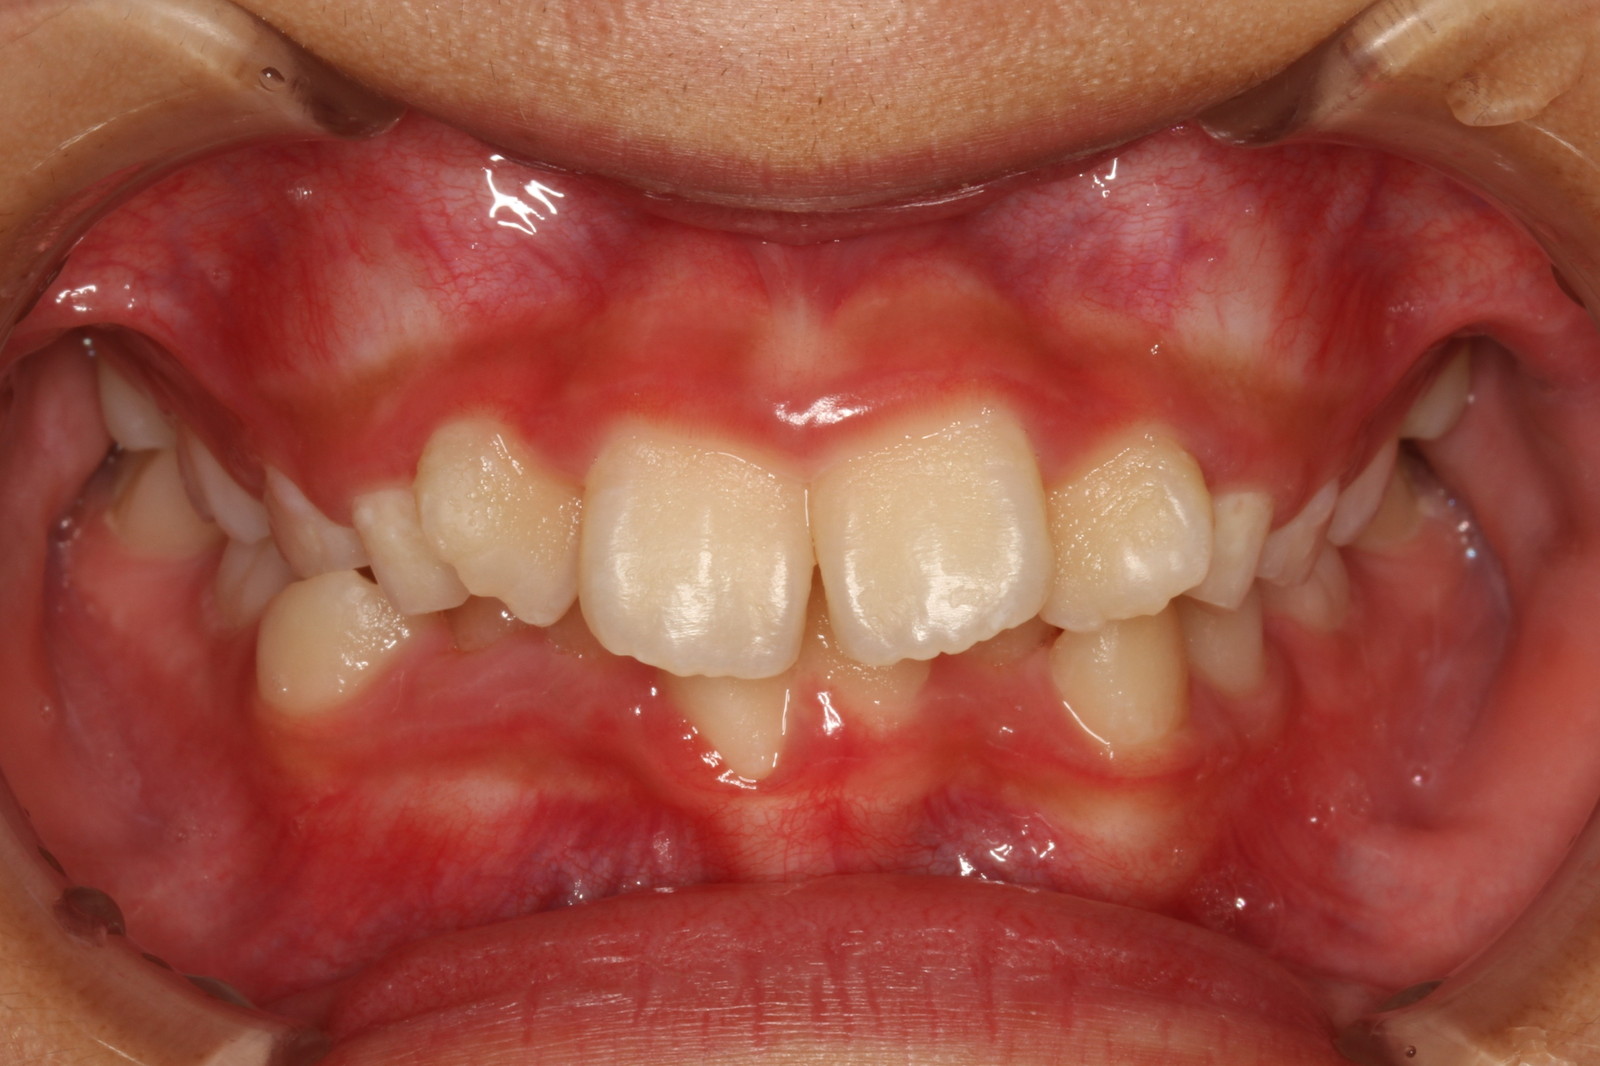

問診を行い、お口の悩みや希望を確認します。レントゲン撮影や口腔内写真の撮影など、必要に応じた精密検査を行います。